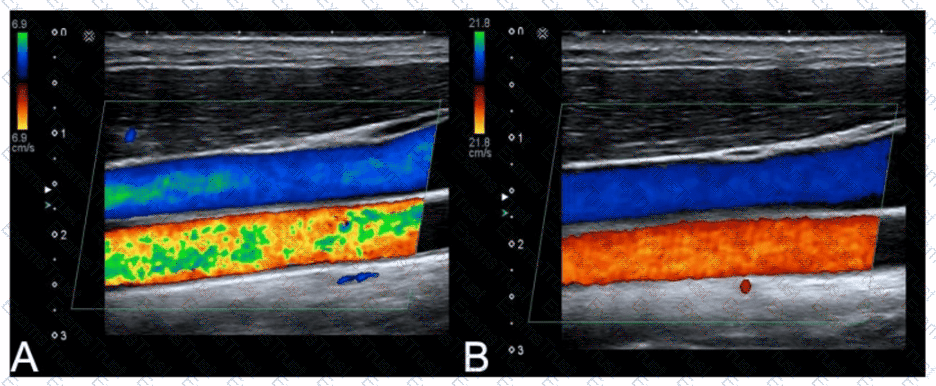

Which adjustment resulted in the change from image A to image B?

Options:

A.

Increased transmit frequency

B.

Increased scale

C.

Decreased color gain

D.

Decreased acoustic power